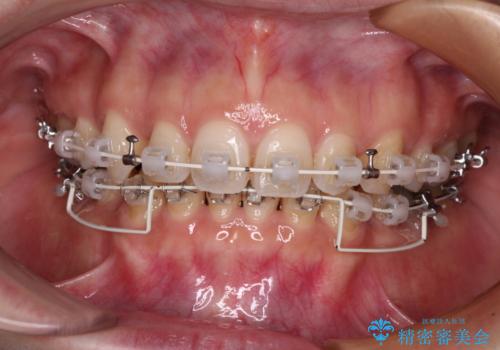

- 審美装置

上下左右第一小臼歯4本を抜歯し、ワイヤー装置にて口元を引っ込めるよう矯正治療を行うこととしました。

奥歯が前方に傾斜していることで深く咬みこむ(ディープバイト)状態であったので、なかなか抜歯したスペースが閉じず、様々な方法でディープバイトを改善しながら治療を進めていくこととなりました。